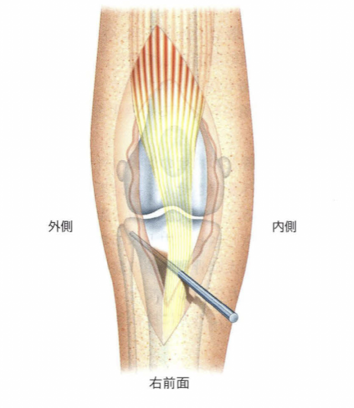

- 関節の縫縮

内方脱臼の場合は外側の、外方脱臼の場合は内側の筋群を重層鱗状縫合という方法で縫縮める手技

- 支帯の解放

脱臼している側に牽引している筋肉を切開し、引っ張る力を弱める手技